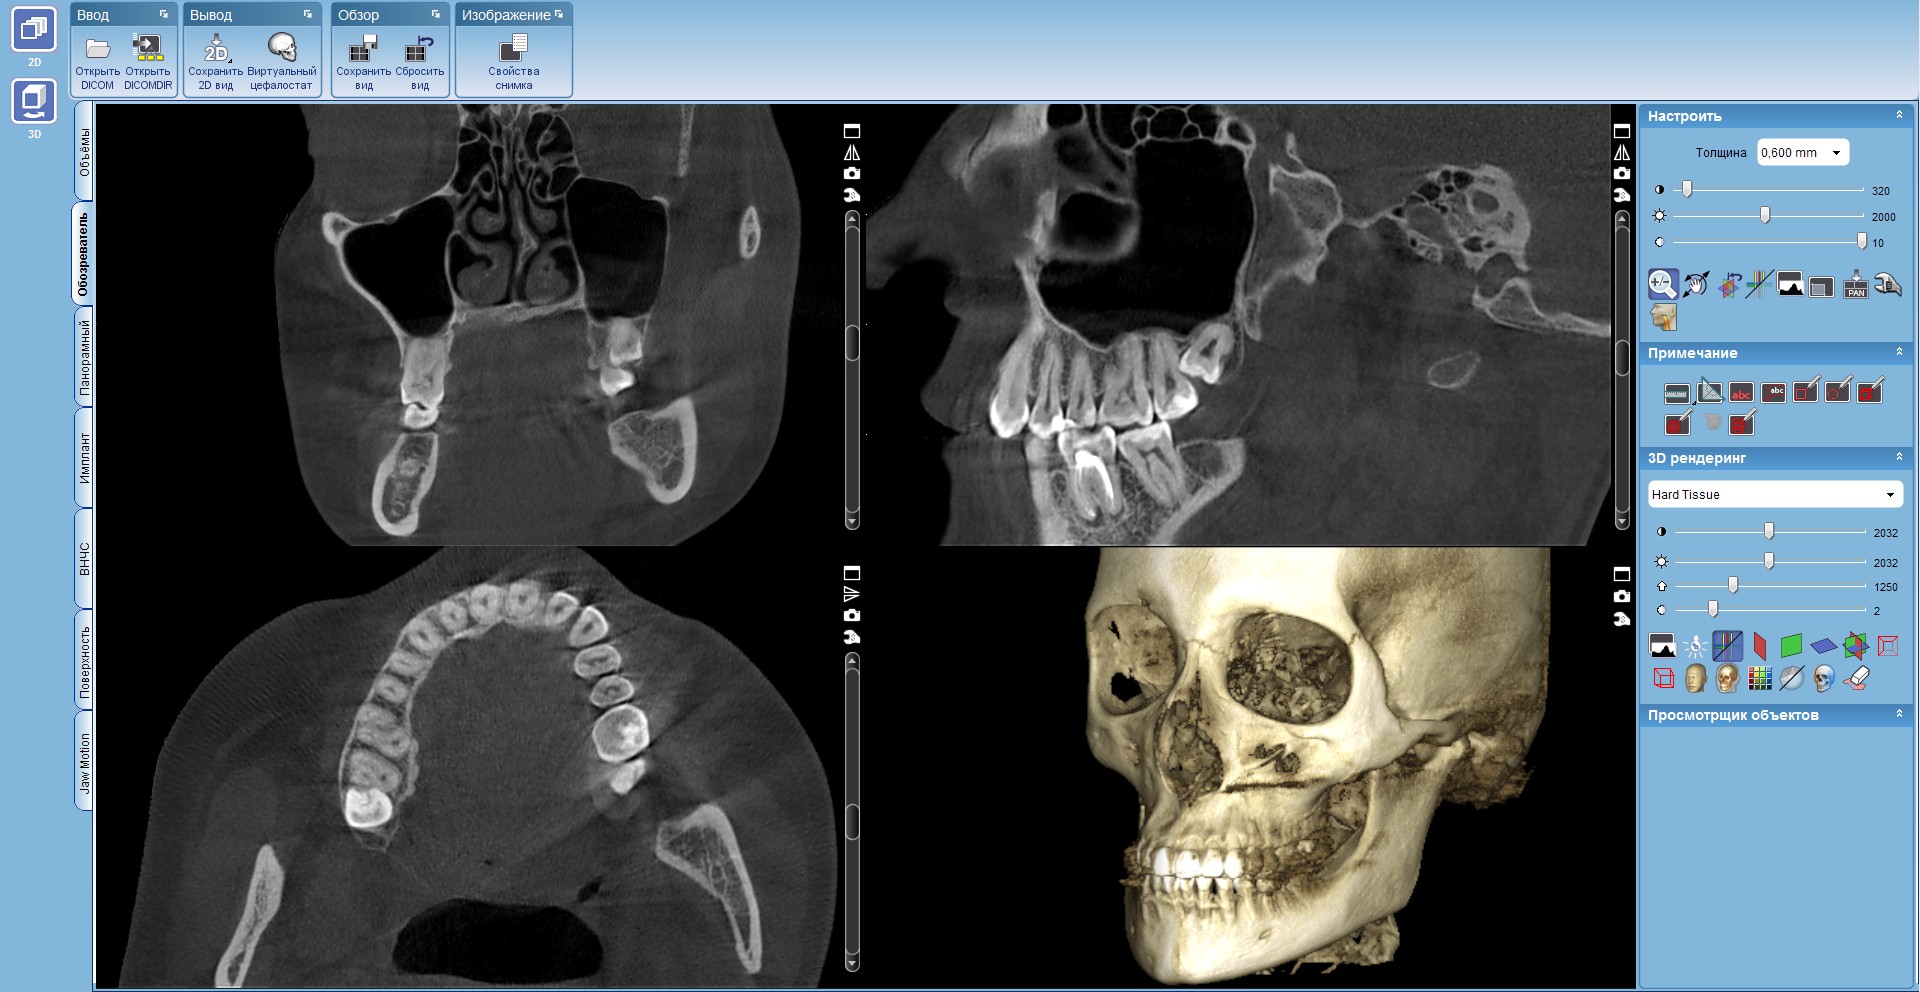

В отличие от рентгенографии, КТ предоставляет трехмерное изображение, что позволяет врачу-радиологу оценить анатомические структуры с несравненно большей точностью. Это особенно важно при подозрении на инфекционные процессы, локализованные в труднодоступных областях организма, таких как глубокие ткани, параназальные пазухи или абсцессы. Возможность визуализации мягких тканей с высокой детализацией делает КТ незаменимым инструментом для диагностики различных инфекционных заболеваний, от осложнений после хирургических вмешательств до туберкулеза и абсцессов.

- Трехмерная реконструкция⁚ Возможность создания трехмерных изображений позволяет врачу оценить пространственное распространение инфекции и определить ее границы.